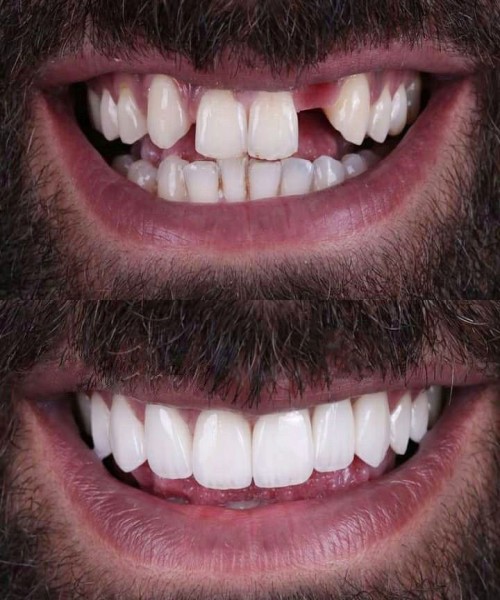

آیا شما هم از مشکلات دندانهای از دست رفته رنج میبرید؟ آیا دندانهای شما از نظر زیبایی یا عملکرد دچار مشکل شدهاند؟ اگر جواب شما بله است، وقت آن رسیده که راهحل بلندمدت و مؤثری را پیدا کنید.

ایمپلنت دندان، نهتنها ظاهری طبیعی و جذاب به شما میدهد بلکه به طور چشمگیری کیفیت زندگی شما را بهبود میبخشد. این روش پیشرفته میتواند جایگزینی دائمی برای دندانهای از دست رفته باشد، که به شما اجازه میدهد دوباره با اعتماد به نفس بخندید، بخورید و حرف بزنید.

با ایمپلنت دندان، نه تنها ظاهر خود را بهبود میبخشید بلکه سلامت دهان و دندان شما هم به شکل قابل توجهی بهتر میشود. ایمپلنتها از تحلیل استخوان جلوگیری میکنند و باعث حفظ ساختار طبیعی فک و دهان میشوند.

ایمپلنت دندان، تنها یک درمان نیست. بلکه فرصتی است برای بازگشت به زندگی راحتتر، زیباتر و بدون دغدغههای دندانی!